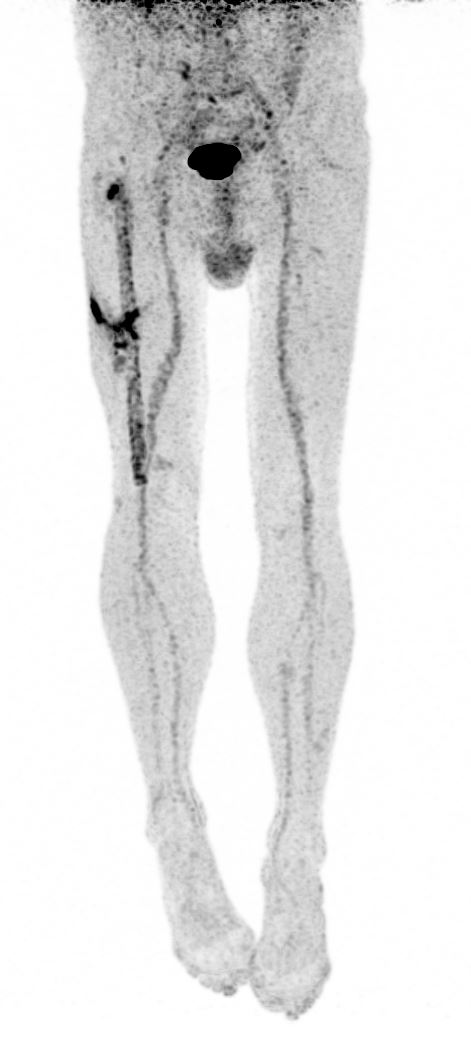

SCINTIGRAPHIE TEP-TDM AU FDG  :

Hypermétabolisme focalisé au niveau de remaniement ostéolytique à l’extrémité proximale de l’enclouage fémoral droit (SUVmax : 8.3) en correspondance avec un foyer d’hyperfixation marqué sur la scintigraphie osseuse.

Infiltration des parties molles hypermétaboliques (SUVmax : 7.6) sur la face latérale de la cuisse droite dans son tiers moyen, avec renforcement de fixation en regard de deux probables trajets fistuleux, le premier vers les masses musculaires de la loge postérieure de la cuisse, le second s’étendant en intra-médullaire à la jonction 1/3 moyen- 1/3 distal du fémur le long de la vis de fixation proximale. Il existe au contact un foyer hypermétabolique (SUVmax : 6.1) à l’interface os – matériel fortement suspect de localisation

septique, en correspondance également avec un foyer d’hyperfixation modéré en scintigraphie osseuse.

Par ailleurs, hypermétabolisme modéré de l’ensemble de l’interface os – tige fémorale compatible avec des remaniements ostéoblastiques (hyperfixation

en scintigraphie osseuse).

Conclusion :

Aspect compatible avec deux foyers d’ostéite fémorale droite au contact du matériel d’ostéosynthèse : le premier au niveau du grand trochanter, le second à la jonction tiers moyen – tiers distal communiquant avec la collection sous-cutanée via un trajet fistuleux.